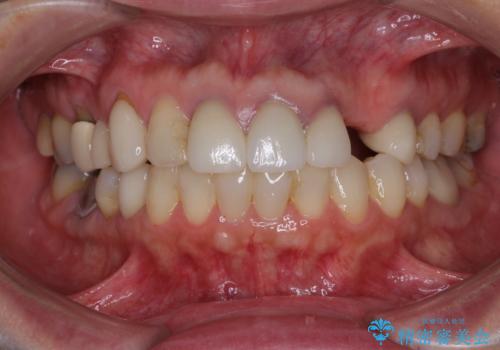

- 他院で矯正治療を終えたものの、むし歯や欠損部の治療が進められないとのことで来院された患者様です。

欠損部や、銀歯やむし歯の大きな歯はセラミッククラウンやブリッジに、小さいむし歯はセラミックインレーにて治療を行うこととしました。